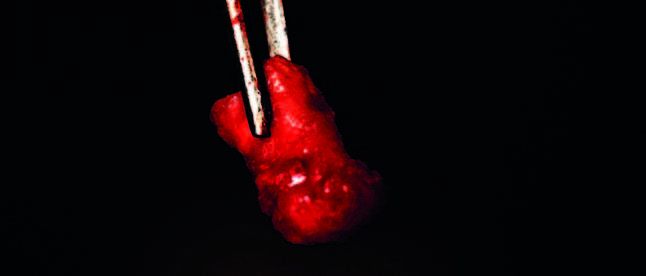

La raíz mesial presentaba un material adherido que tenía una consistencia heterogénea (Figura 5). En el fondo del alveolo, se observó tejido que se desprendía fácilmente, caracterizado por un material igualmente heterogéneo, consistente en tejido fibroso intercalado con zonas de mayor densidad, compatibles con una osificación parcial en desarrollo. Este material junto a las raíces se remitió para su análisis histopatológico.